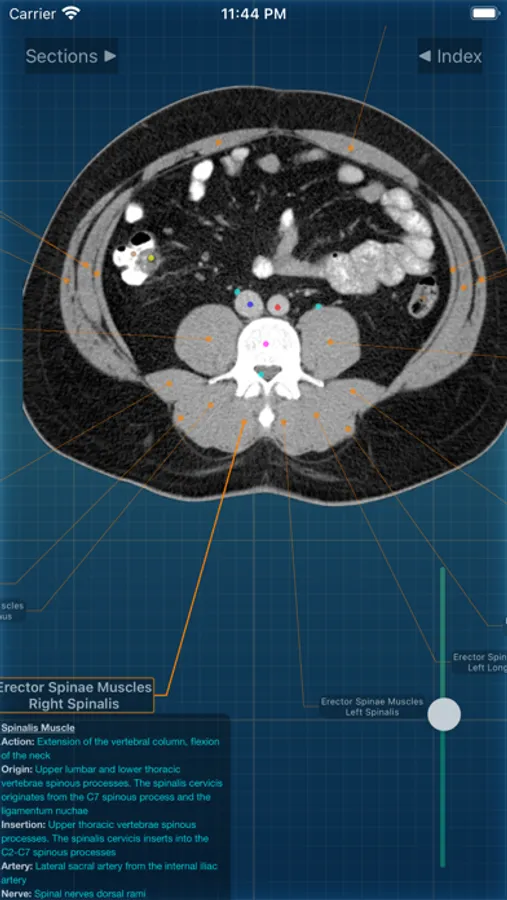

X-Anatomy is a transaxial cross-sectional human anatomy interactive medical imaging atlas using CT images, designed for medical professionals & all students of anatomy.

* Includes hundreds of images from actual human patient body scans.

* Detailed anatomic notes about muscles, vessels, and key anatomic structures

* Complete color-coded index of anatomic structures

* FOLLOW the positions and pathways of your selected anatomic structures automatically as you SCROLL through the image slices.

INCLUDED body section modules cover the major body sections from head to pelvis: CT Brain, CT Neck, CT Sinuses, CT Chest, CT Lungs, CT Abdomen & Male Pelvis, CT Abdomen & Female Pelvis.